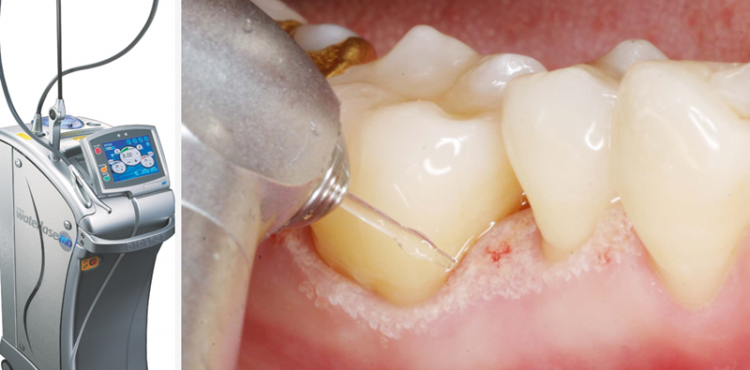

물방울레이저로 치아와 잇몸 사이의 틈에 에너지를 주사해 그 어떤 절개나 봉합 없이 제거를 도와드립니다.

물방울 레이저란 물 분자에 레이저 열을 담은 치료 기기인데요

일반 레이저와는 달리 물방울 분자가 열을 식히고 줄여주기 때문에 출혈과 통증을 현저하게 줄여

부기도 현격하게 완화시키고 물방울레이저가 출시되자마자 사용을 시작해 모든 치료에 접목 시키면서

기술을 향상시켜 진료 수준을 높이게 되었습니다.